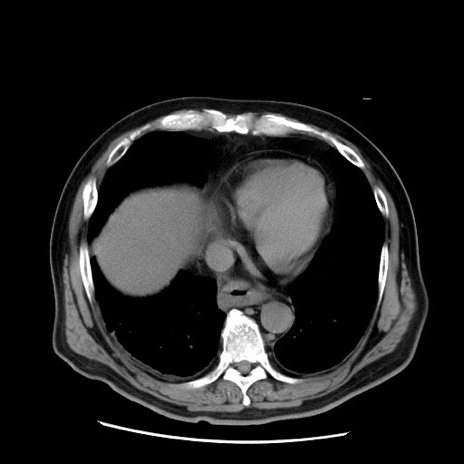

症例20(横断像)

【症例】 60歳代男性

【主訴】 腹部膨満、嘔吐

【現病歴】5日前頃より倦怠感を認め食事量減少し4日前の朝嘔吐、食事摂取困難となった。 3日前近医受診し点滴施行され整腸剤などを処方された。 当日他院を受診し、腹部膨満著明、炎症反応の上昇(CRP10.8、WBC11200)あり、紹介受診となる。

【身体所見】 意識JCS1 受け答えがはっきりしないBP 111/57mHg、 P 67bpm、、BT35.2°C、SpO2 97%(RA)、 腹部:膨隆、打診で鼓音あり、全体的に圧痛有り、腸蠕動音(-)、反跳痛ははっきりせず。

【データ】WBC 11400、CRP 14.20